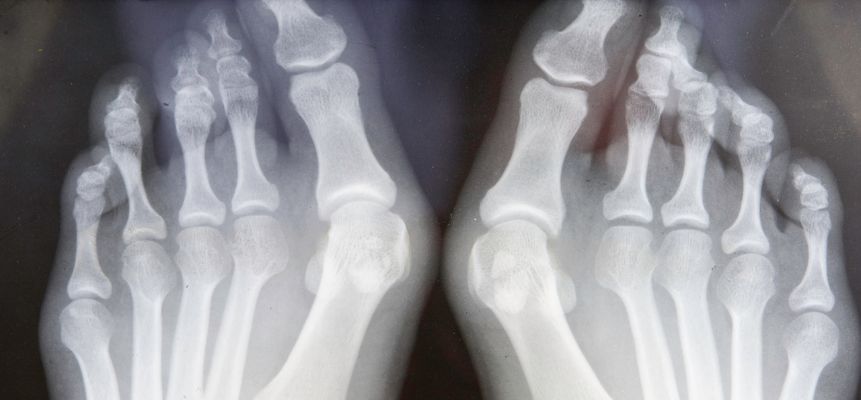

Juanetes

También conocido como hallux valgus, se trata de una deformidad del dedo gordo que se desvía hacia los demás dedos, formando una protuberancia ósea. Causa dolor, inflamación y dificultad para calzarse. Su origen puede ser hereditario o por el uso prolongado de calzado inadecuado.

Como tratamiento se usan plantillas personalizadas, fisioterapia y en casos graves, se realiza una cirugía podológica. Lo ideal es realizarte un estudio de la pisada para ver cuál es el tratamiento más adecuado para tu pie en avanzada edad.